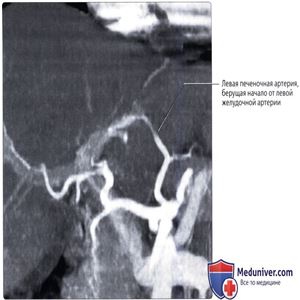

КТ с контрастированием, реконструкция ПМИ, корональный срез: определяется точка отхождения левой печеночной артерии от левой желудочной артерии—часто встречающийся вариант развития, лучше визуализирующийся при КТ-ангиографии, чем при катетерной ангиографии. Ветви системы вороной вены контрастируются слабее, что обусловлено выбором времени проведения КТ для преимущественной визуализации артерий. Левая печеночная артерия «замещена» левой желудочной артерией - у 10% людей.